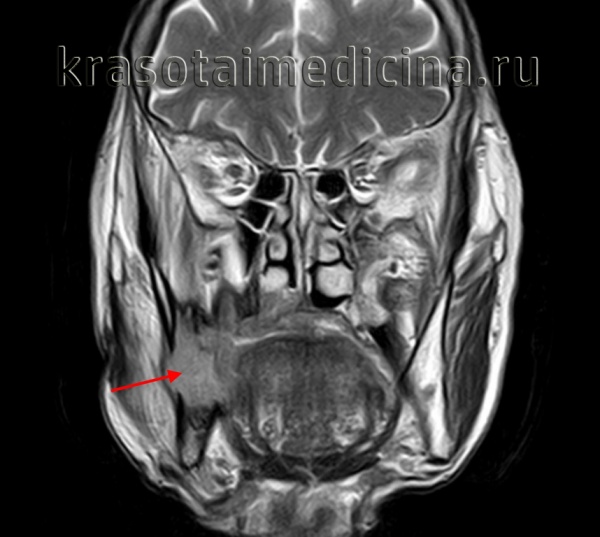

(Слева) На аксиальной МРТ (Т2 ВИ FS) определяется амелобластома верхней челюсти с солидным и кистозным компонента ми, выглядящая многокамерной. Обратите внимание на типичный гиперинтенсивный Т2 сигнал в кистозных компонентах и вздутие задней стенки верхнечелюстной пазухи.

(Справа) На корональной MPT (Т1 ВИ C+ FS) у этого же пациента определяется контрастное усиление перегородок, обычно наблюдающееся при амелобластоме. Местно агрессивную природу этой опухоли доказывает ее распространение в полость носа и ячейки решетчатого лабиринта.